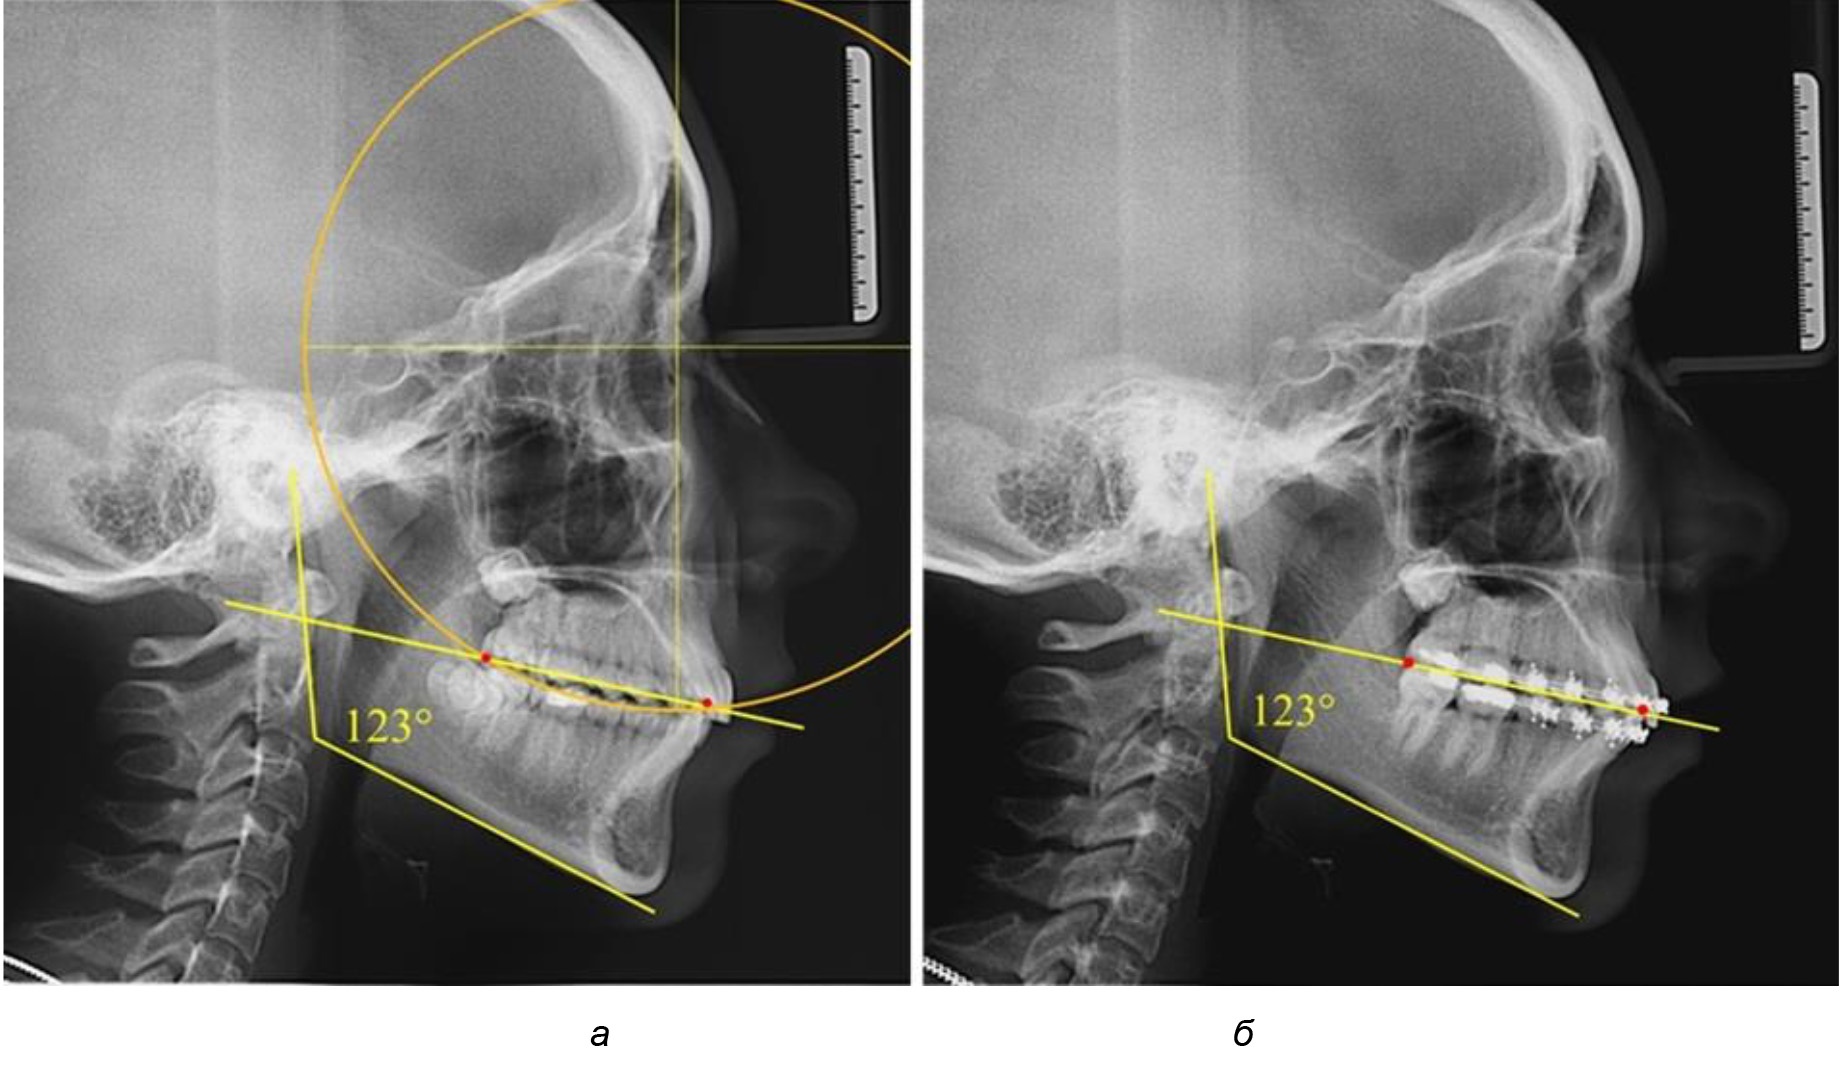

Глубина кривой Spee в среднем по 2-й подгруппе составила (5,69 ± 1,57) мм, что было достоверно больше, чем у людей с физиологической окклюзией (р ˂ 0,05). Достоверных различий с показателями, полученными при анализе ТРГ и ОПТГ, нами не отмечено (р ˃ 0,05). Отношение радиуса окружности к сагиттальному размеру окклюзионной линии в среднем по подгруппе составляло 1,372 ± 0,042 и не соответствовало числу Фибоначчи, что может быть использовано в качестве диагностического критерия определения патологической формы кривой Spee. После лечения пациентов техникой «прямой» дуги было отмечено незначительное увеличение сагиттального размера окклюзионной лини в среднем на (2,12 ± 0,77) мм. Однако окклюзионная линия практически касалась окклюзионного контура всех жевательных зубов, и отмечалось практически полное отсутствие кривой Spee.

Таким образом, проведенное лечение техникой «прямой» дуги способствует нормализации окклюзионного равновесия и торку передних зубов, однако не соответствует оптимальному окклюзионному статусу, характеризующему физиологическую окклюзию. При этом величина нижнечелюстного угла оставалась на прежнем уровне (рис. 5).

Рис. 5. Особенности ТРГ при патологической кривой Spee до лечения (а) и после лечения (б) техникой «прямой» дуги

Обращает на себя внимание, что глубина кривой Spee в анализируемой подгруппе практически не отличалась от показателей, полученных у людей с физиологической окклюзией, и составляла (4,23 ± 1,58) мм. Отношение радиуса окружности к сагиттальному размеру окклюзионной линии в среднем по подгруппе составляло 1,623 ± 0,02 и соответствовало числу Фибоначчи.

После лечения пациентов техникой «прямой» дуги, так же как и в 1-й подгруппе, было отмечено увеличение сагиттального размера окклюзионной лини в среднем на (2,38 ± 0,83) мм. Окклюзионная линия практически касалась окклюзионного контура всех жевательных зубов, и отмечалось практически полное отсутствие кривой Spee, так же как и у людей 1-й подгруппы 2-й группы (рис. 6).

Рис. 6. Особенности ТРГ при оптимальной кривой Spee до лечения (а) и после лечения (б) техникой «прямой» дуги

Таким образом, проведенное лечение техникой «прямой» дуги способствует нормализации окклюзионного равновесия и торку передних зубов, однако не соответствует оптимальному окклюзионному статусу, характеризующему физиологическую окклюзию. При этом величина нижнечелюстного угла оставалась на прежнем уровне.